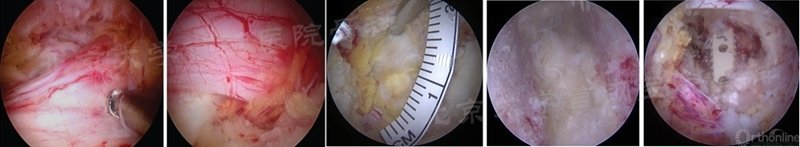

(3)BE-EFLIF:常规进行椎间孔成形、同侧关节突关节外侧部分切除,以实现椎间孔扩大,去除部分孔区黄韧带以实现Kambin三角区的显露。最后切开Kambin三角区的纤维环以处理椎间隙(如图24)。但该术式无法常规进行过顶减压,需要进行Q和Q’切口(见笔者辅助切口篇)。

图24 BE-EFLIF减压过程的镜下视野(图片来源于对文献中图片的整理)